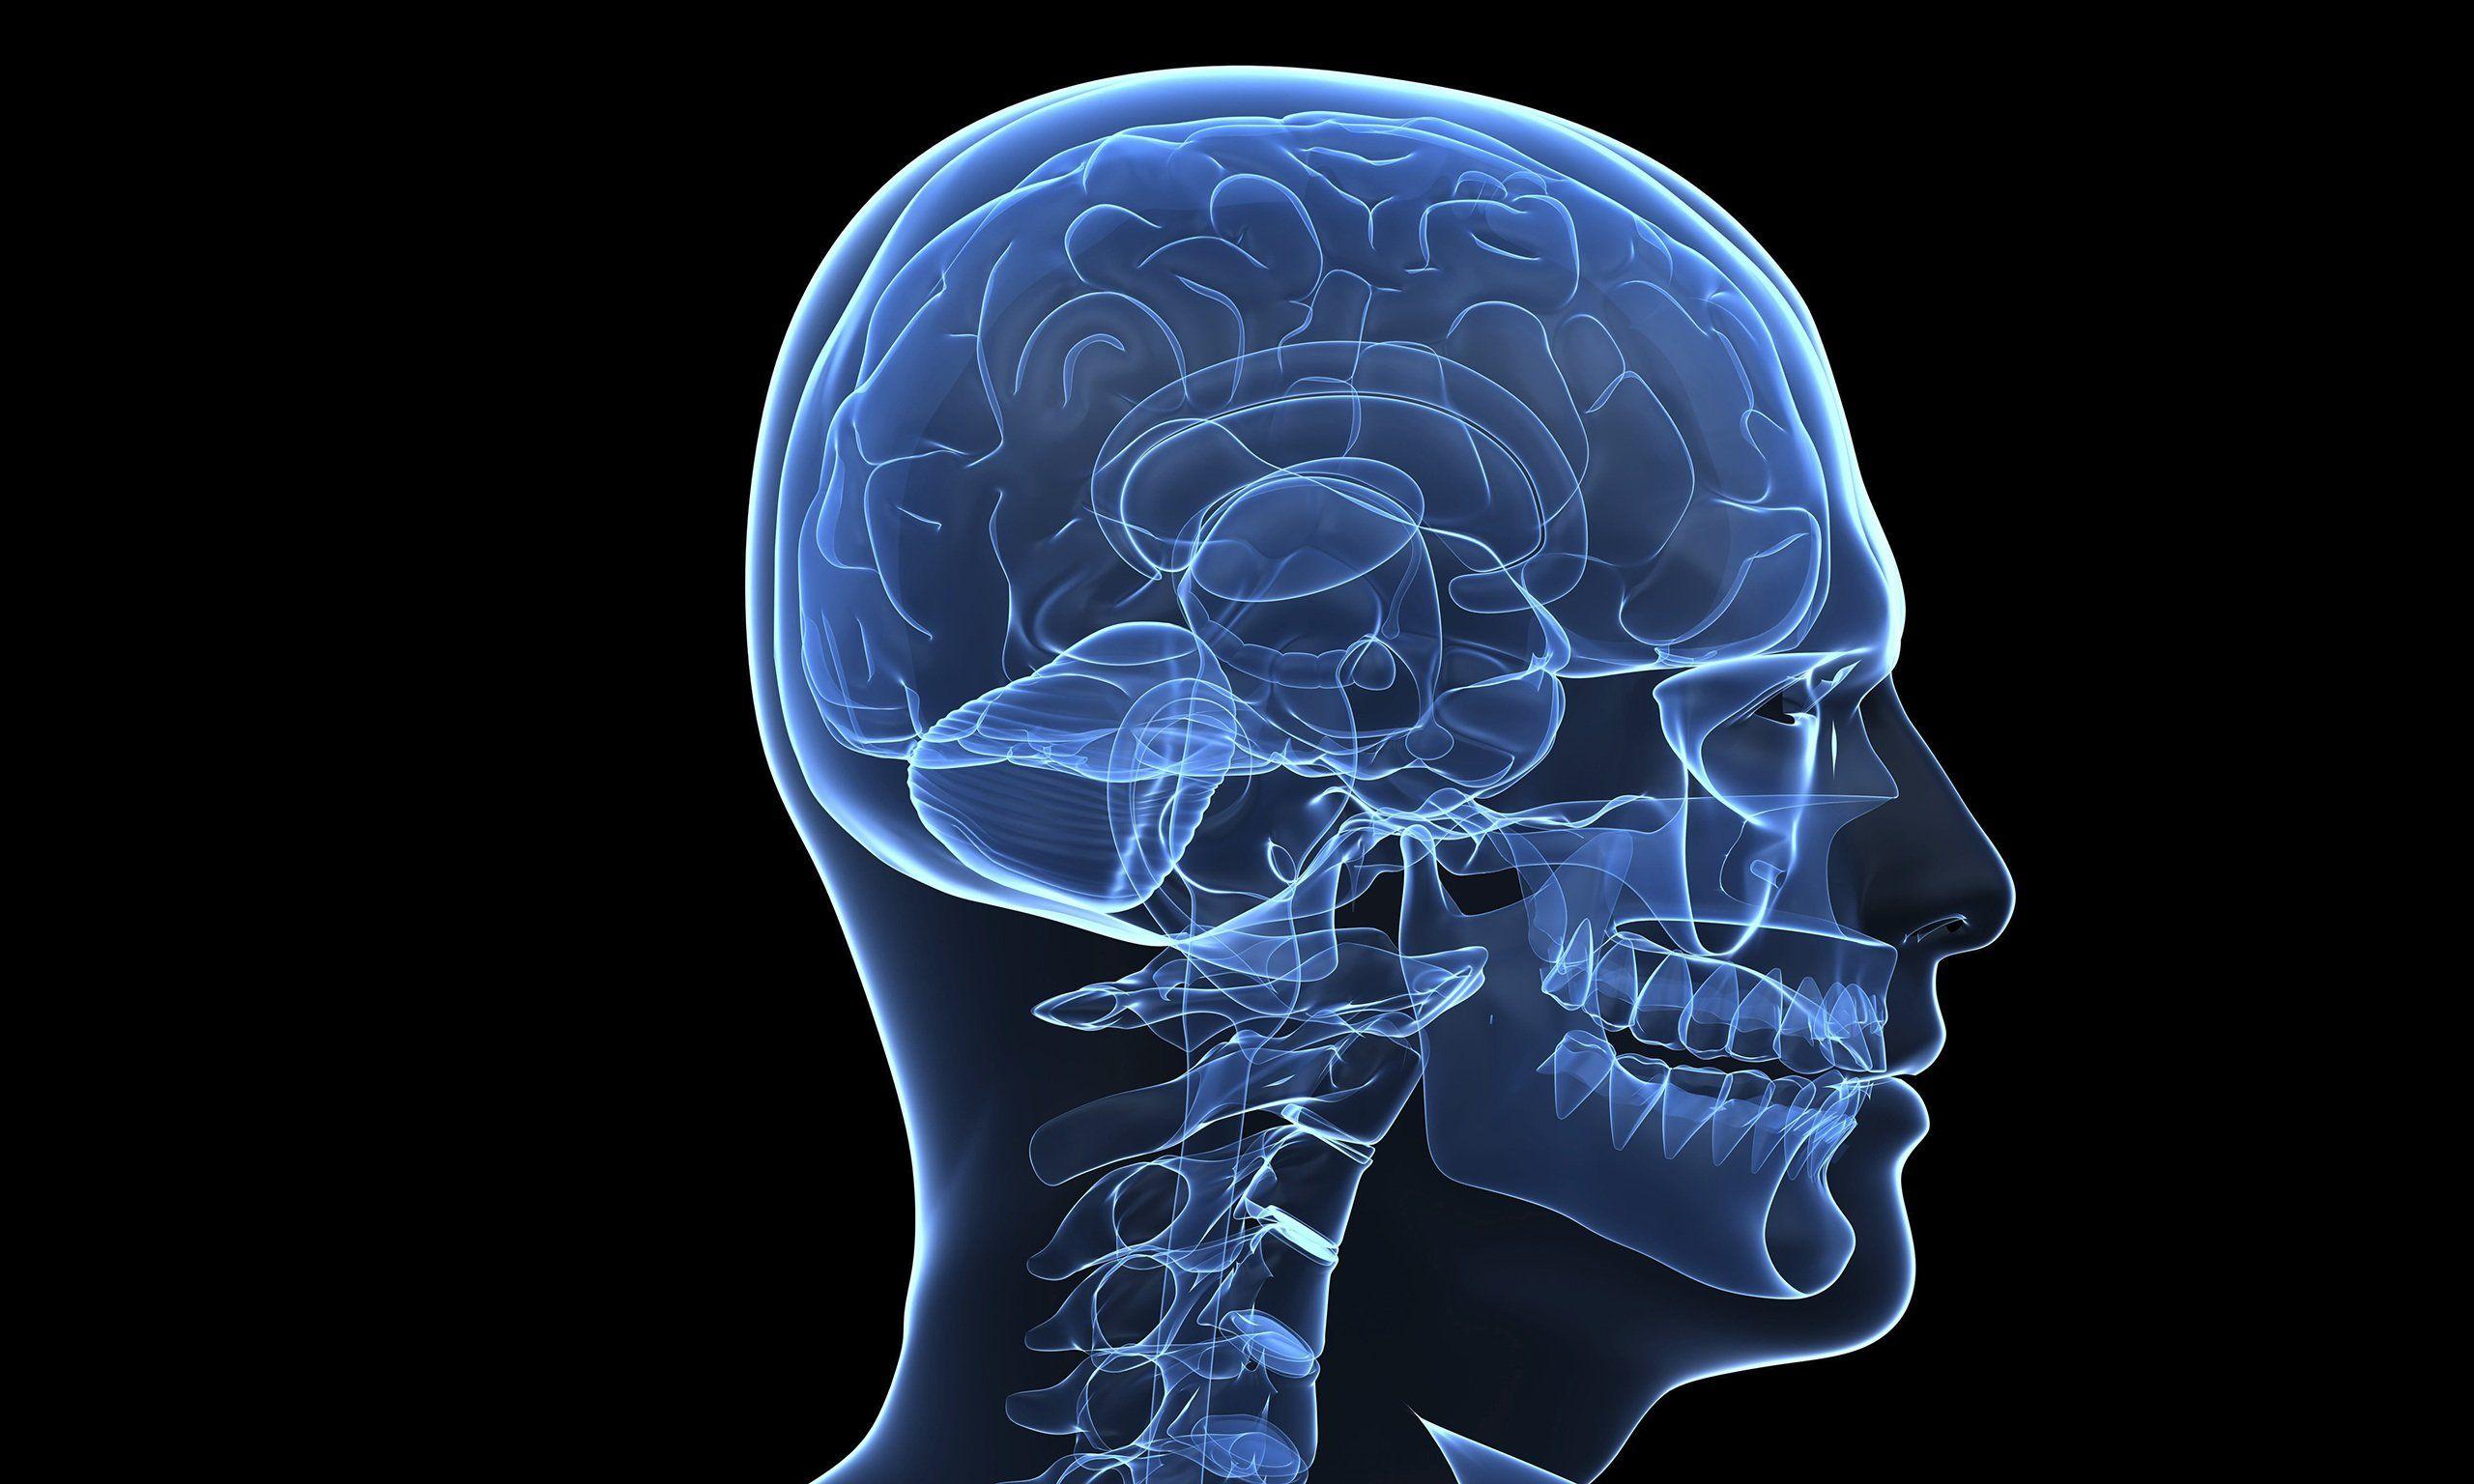

Brain, Anatomy, Medical, Head, Skull, Digital, 3 D, X Ray, Xray

wallup.netbrain wallpaper anatomy medical skull digital xray ray head wallpapers psychedelic cool hd 3d background desktop px wallpaperaccess wallpapertag original

wallup.netbrain wallpaper anatomy medical skull digital xray ray head wallpapers psychedelic cool hd 3d background desktop px wallpaperaccess wallpapertag original

10+ X-ray HD Wallpapers And Backgrounds

wall.alphacoders.comray wallpaper hd anatomy brain background human man wallpapers wall 3d backgrounds intelligence artificial biology

wall.alphacoders.comray wallpaper hd anatomy brain background human man wallpapers wall 3d backgrounds intelligence artificial biology